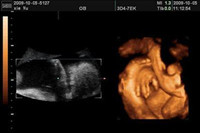

彩超與B超的區(qū)別在哪里呢?彩超與唐氏篩查的區(qū)別又在哪里呢?然而,這些還不是很打緊的問題,最重要的是四維彩超是需要提前預(yù)約才能做的,準(zhǔn)媽媽們知道四維彩超哪里做最好嗎?什么時(shí)...

目前最先進(jìn)的彩色超聲檢測儀器,是大家公認(rèn)的四維彩超,說起四維彩超的優(yōu)點(diǎn)那可多著了,通常懷孕的準(zhǔn)媽媽們在孕期一定要做一次四維彩超,它可以監(jiān)測胎兒在母體的活動實(shí)況,...

孕期的各項(xiàng)檢查,準(zhǔn)媽媽們都必須按時(shí)完成,這即是對孕婦自身,也是對胎兒寶寶負(fù)責(zé)。提起四維彩超相信大多數(shù)的媽咪們都很清楚,四維彩超比普通的B超在技術(shù)和等級上都有一定飛越...